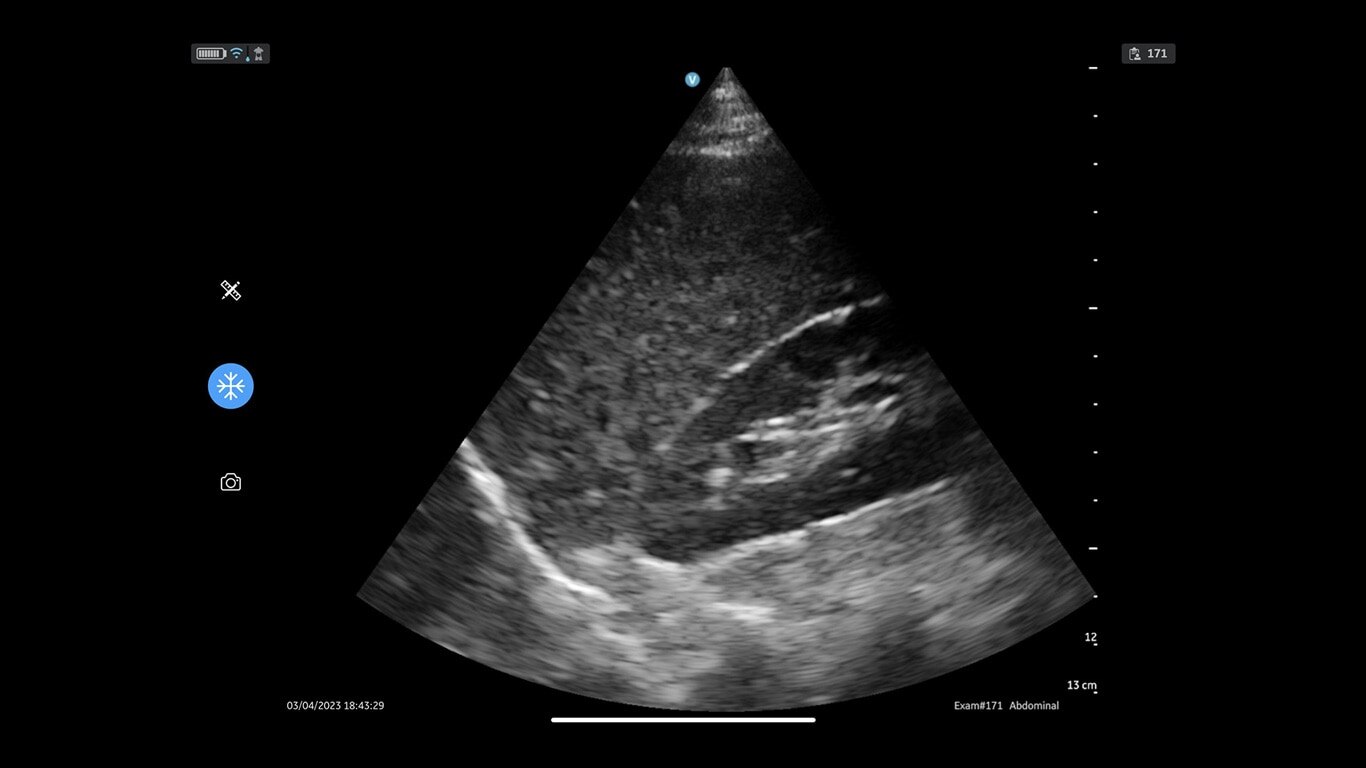

Vscan Air SL handheld ultrasound offers wireless freedom and maximum portability with two transducers in a single device. Delivers crystal-clear images at the point of care. Sector-phased array transducer is ideal for rapid cardiac assessments. The linear array transducer allows you to move from a cardiac to a vascular assessment without missing a beat.

Quality imaging capabilities for multiple clinical healthcare applications.

Ideal for focused cardiac assessments, thoracic to musculoskeletal, nerves, and more. Complete both shallow and deep ultrasound scans with one probe without compromising image quality.